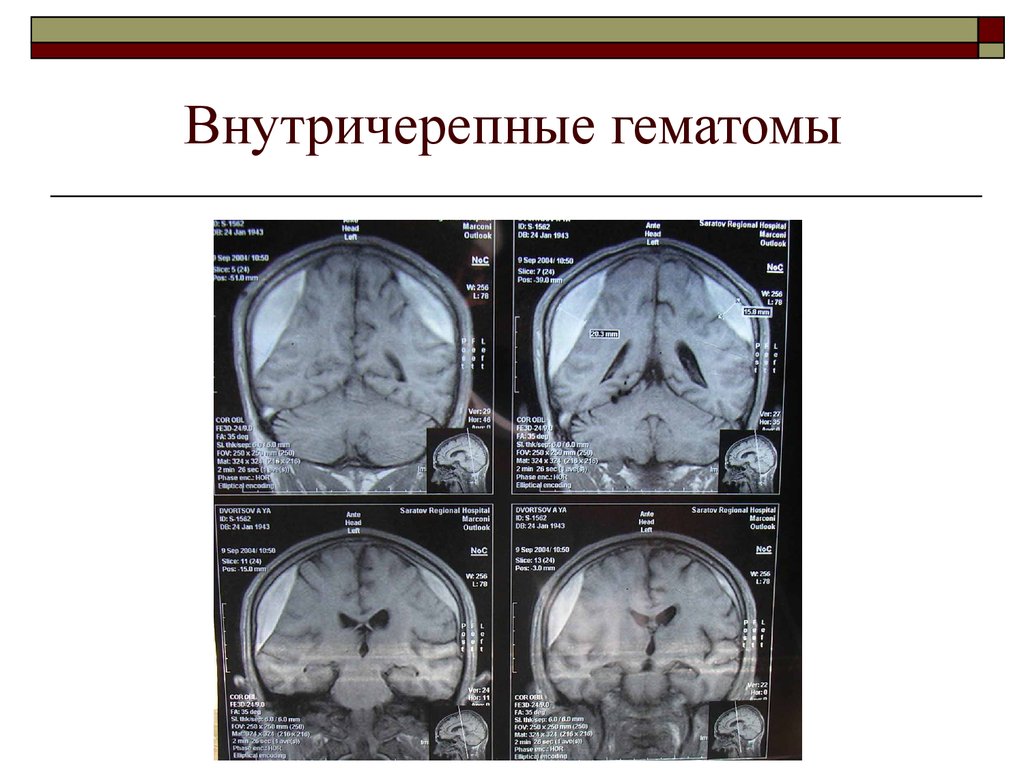

Внутричерепные кровоизлияния у новорожденных презентация - 92 фото